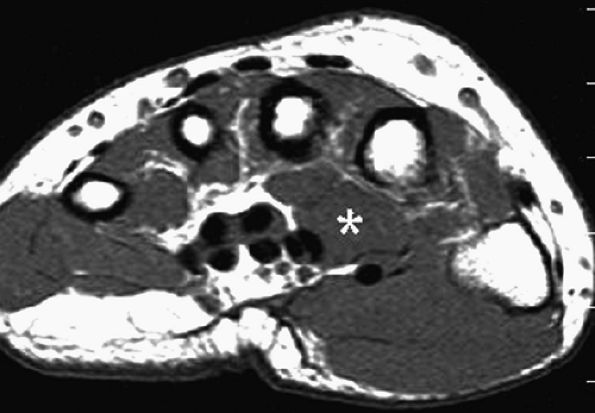

-

Size of the nerve. The cross-sectional area of the median nerve is significantly larger in patients with carpal tunnel syndrome than in asymptomatic individuals.116 However, the cutoff size of the cross-sectional area between a normal and a pathologic median nerve is unclear. To evaluate proximal enlargement of the median nerve on axial MR images, comparison of the cross-sectional area of the nerve at the level of the radioulnar joint and at the level of the pisiform bone should be obtained. In patients with carpal tunnel syndrome, the median nerve at the level of the pisiform may be twice or three times as large as at the level of the radioulnar joint.117

Nerve flattening. Flattening of the nerve can be evaluated using flattening ratios, defined as the ratio between the major and minor axes of the nerve both at the level of the distal radioulnar joint and at the level of the hook of the hamate.117 A flattening ratio greater than 3 at the level of the hook of the hamate may indicate median nerve pathology.

Flexor retinaculum bowing. Bowing of the flexor retinaculum likely reflects increased pressure or volume within the carpal tunnel. In normal individuals, the flexor retinaculum at the level of the hook of the hamate should be flat or slightly convex. The degree of bowing is determined by dividing the distance of palmar displacement of the retinaculum by the distance between the hook of the hamate and the tubercle of the trapezium. In normal patients, the ratio varies from 0 to 0.15 (mean 0.05). In carpal tunnel syndrome, however, the ratio varies from 0.14 to 0.26 (mean 0.18).117

FIGURE 12.45 ● Carpal tunnel syndrome. (A) Axial fat-suppressed T2-weighted image through the distal carpal tunnel demonstrates enlargement of the median nerve with bowing of the flexor retinaculum. The bowing ratio of the flexor retinaculum, determined by dividing its palmar displacement by the distance between the hook of the hamate to the tubercle of the trapezium, was 0.18 (normal ratio, 0 to 0.15). (B) Axial T2-weighted image through the proximal metacarpal region shows a swollen and hyperintense median nerve (arrow).